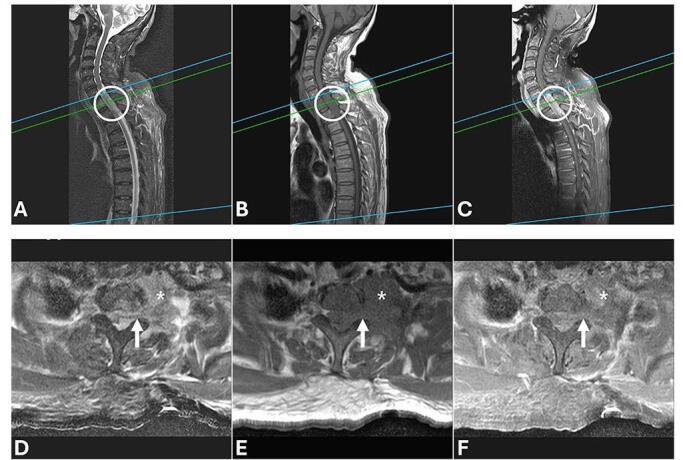

PRESENTATION OF CASE

A 67-year-old woman was diagnosed with left upper lobe (LUL) lung tumor, and surgical pathology confirmed PC with spindle and giant cell components. Following surgery, she developed progressive paraparesis with ascending hypesthesia. Contrast-enhanced cervicothoracic spine MRI revealed direct invasion of the T1-T3 vertebrae and pedicles by the LUL tumor, resulting in spinal cord compression and paraspinal muscle involvement. Neurogenic shock subsequently developed, and the patient died 2 weeks later.

病例介绍

一名67岁女性被诊断为左上叶(LUL)肺肿瘤,手术病理证实为具有梭形和巨细胞成分的PC。手术后,她出现进行性双下肢轻瘫并伴有感觉减退。颈椎胸椎增强磁共振成像(MRI)显示LUL肿瘤直接侵犯T1 - T3椎体和椎弓根,导致脊髓受压和椎旁肌肉受累。随后发生神经源性休克,患者在2周后死亡。